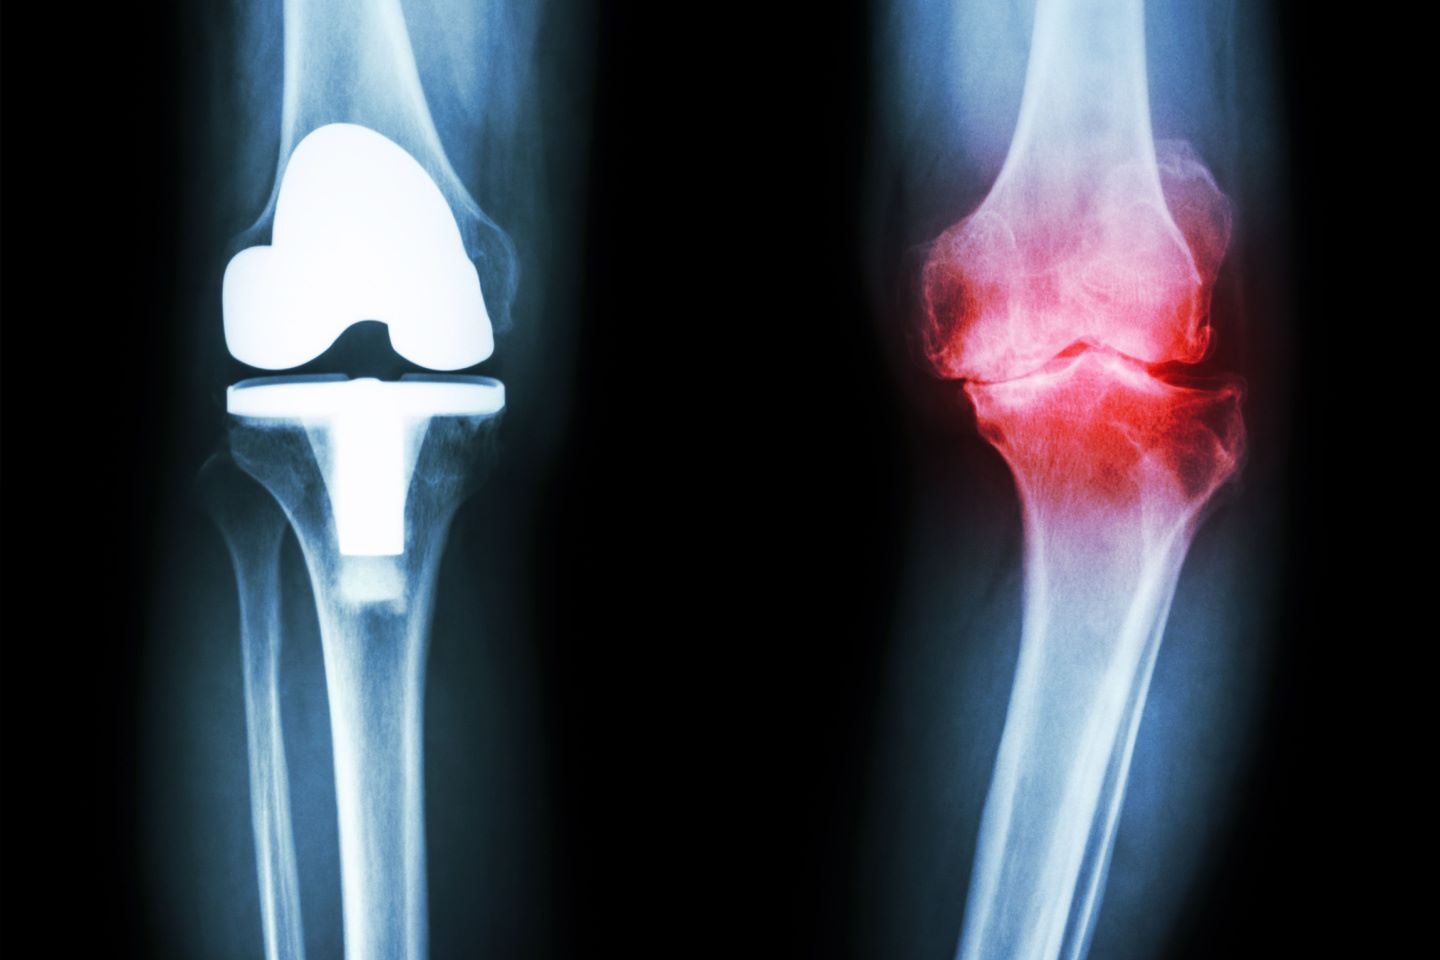

Cilj liječenja umjetnim zglobovima je smanjenje boli, povećanje pokretljivosti zgloba i nadomještanje funkcije postojećega oštećenog zgloba. Kad govorimo o indikacijama za kirurško liječenje zamjene zgloba, ograničit ćemo se na najčešće lokacije - zglob kuka i koljenski zglob.

- osteoartritis težeg stupnja (stari naziv koksartroza za kuk, odnosno gonartroza za koljeno)

- reumatoidni artritis s teškim oštećenjem zglobova (deformiteti)